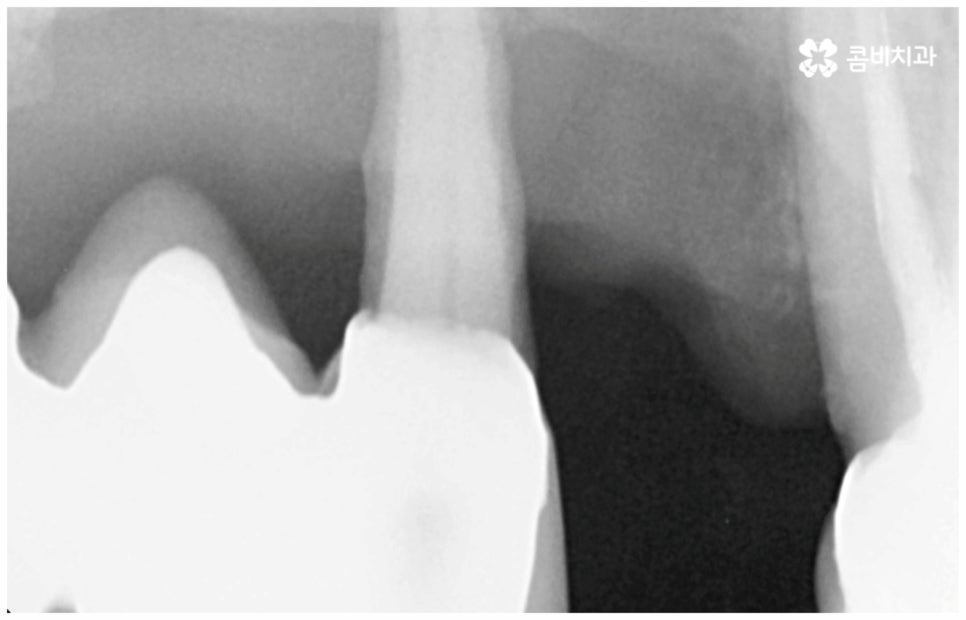

그러나 노화나 구강 질환을 원인으로 한 경우에는 식립 절차가 좀 더 복잡해 질 수 있는데요. 잇몸병을 예로 들어 생각해 보면 자연스러운 노화 및 관리 소홀로 인해 치아 주변 조직 (잇몸, 치주인대, 치조골 등) 에 염증 반응이 생기는 병인 치주 질환이 많이 심해졌을 때 상황에 따라 해당 자연 치아를 살리지 못하고 발치를 해야할 수도 있는 거예요. 이렇게 치주질환을 이유로 임플란트 식립을 진행할 때에는 식립 성공률을 높이고 임플란트수명 을 늘리기 위해 먼저 치주질환 치료를 선행해 줘야 하며, 환자분들의 상황에 따라 뼈이식 또는 상악동 거상술을 통해 잇몸뼈를 보충해 줘야 할 수도 있어요. 치조골이 이미 많이 녹아 있거나 병증이 극심하다면 임플란트 식립 난이도가 매우 높아지거나 때로는 불가능해 질 수 있기 때문에 다양한 임상 경험을 통해 풍부한 노하우를 가지고 있는 의료진에게 진단 및 치료를 받는 것이 굉장히 중요한 포인트라고 할 수 있습니다.

보통 정확한 위치에 식립하고 철저하게 사후 관리를 해 준다면 임플란트수명 은 거의 반영구적이라고 할 정도로 오랫동안 건강하게 사용할 수 있습니다. 그러기 위해서는 처음 식립할 때 환자분들의 상황에 맞게 체계적인 계획을 세워 정밀한 식립을 진행할 수 있는 시술자의 높은 숙련도 외에도 꼼꼼한 검사를 위한 3D-CT 와 같은 정밀 진단 장비를 갖추고 있는지 여부를 살펴보실 필요가 있어요. 이를 통해 환자분들 각각의 구강 구조, 치조골 상태 (밀도나 두께 등), 신경이나 혈관과 같은 주변 조직 등을 정확하게 분석한 다음 오랜 임상데이터를 바탕으로 높은 성공률을 보이고 있는 정품 재료를 사용하여 식립을 진행하는 것이 임플란트수명 을 늘리는데 도움을 주므로 이런 점들 역시 신경써서 살펴보시길 권유드리고 있습니다.